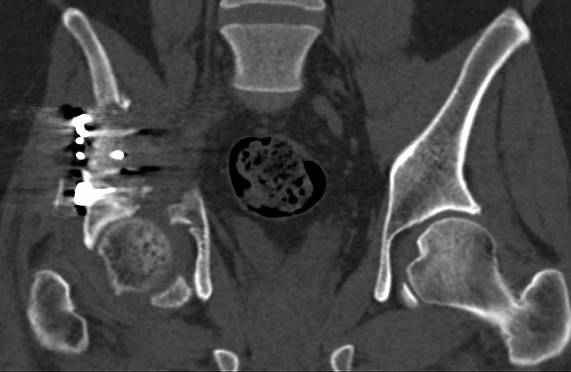

Интересно было бы посмотреть рентгенограммы до операции. У меня впечатление, что я не все вижу, что тут есть... Уважаемые Господа "тазисты" и "тазологи", к какому типу переломов вертлужной впадины по Летурнелю вы бы отнесли это случай?

Из переломов проходящих через крыло и/или заднюю стенку ни простой перелом "передней колонны" (явно имеется пером задней стенки, и не видно перелома седалищной или лонной), ни простой "поперечный", ни ассоциированный "Т-образный" (т.к есть перелом крыла и не видно перелома седалишной), ни ассоциированный "задняя колонна+задняя стенка", на ассоциированный "поперечный+задняя стенка", ни ассоциированный "передняя колонна+задняя гемисфера" (не видно перелома седалищной), ни ассоциированный "обе колонны" (не видно перелома лонной седалищной) не подходят под эту классификацию....

к таковым себя не причисляю, но...обычное дело для нашей страны - выкладывать 3D и не показывать стандартные проекции Judet. Дигност представляет те ракурсы, которые по-его мнению наиболее информативны, более того комп сам достраивает какие-то мелкие повреждения по 3D по своему усмотрению. По данной реконструкции можно предполагать высокий двухколонный перелом с оскольчатыми передней и задней колоннами, оскольчатую высокую переднюю колонну с задним полупоперечником или одно из перечисленных с вовлечение КПС. У меня впечатление за второй вариант, но нужно обследовать нормально - проекции, сканы.

высылаю дополнительно сканы.